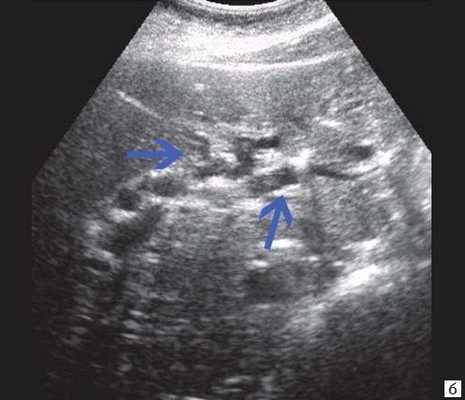

Рис. 3. Эхографическая картина хронического псевдотуморозного панкреатита. Кальцинаты в паренхиме ПЖ.

б) Расширение внутрипечоночных протоков (синяя стрелка).